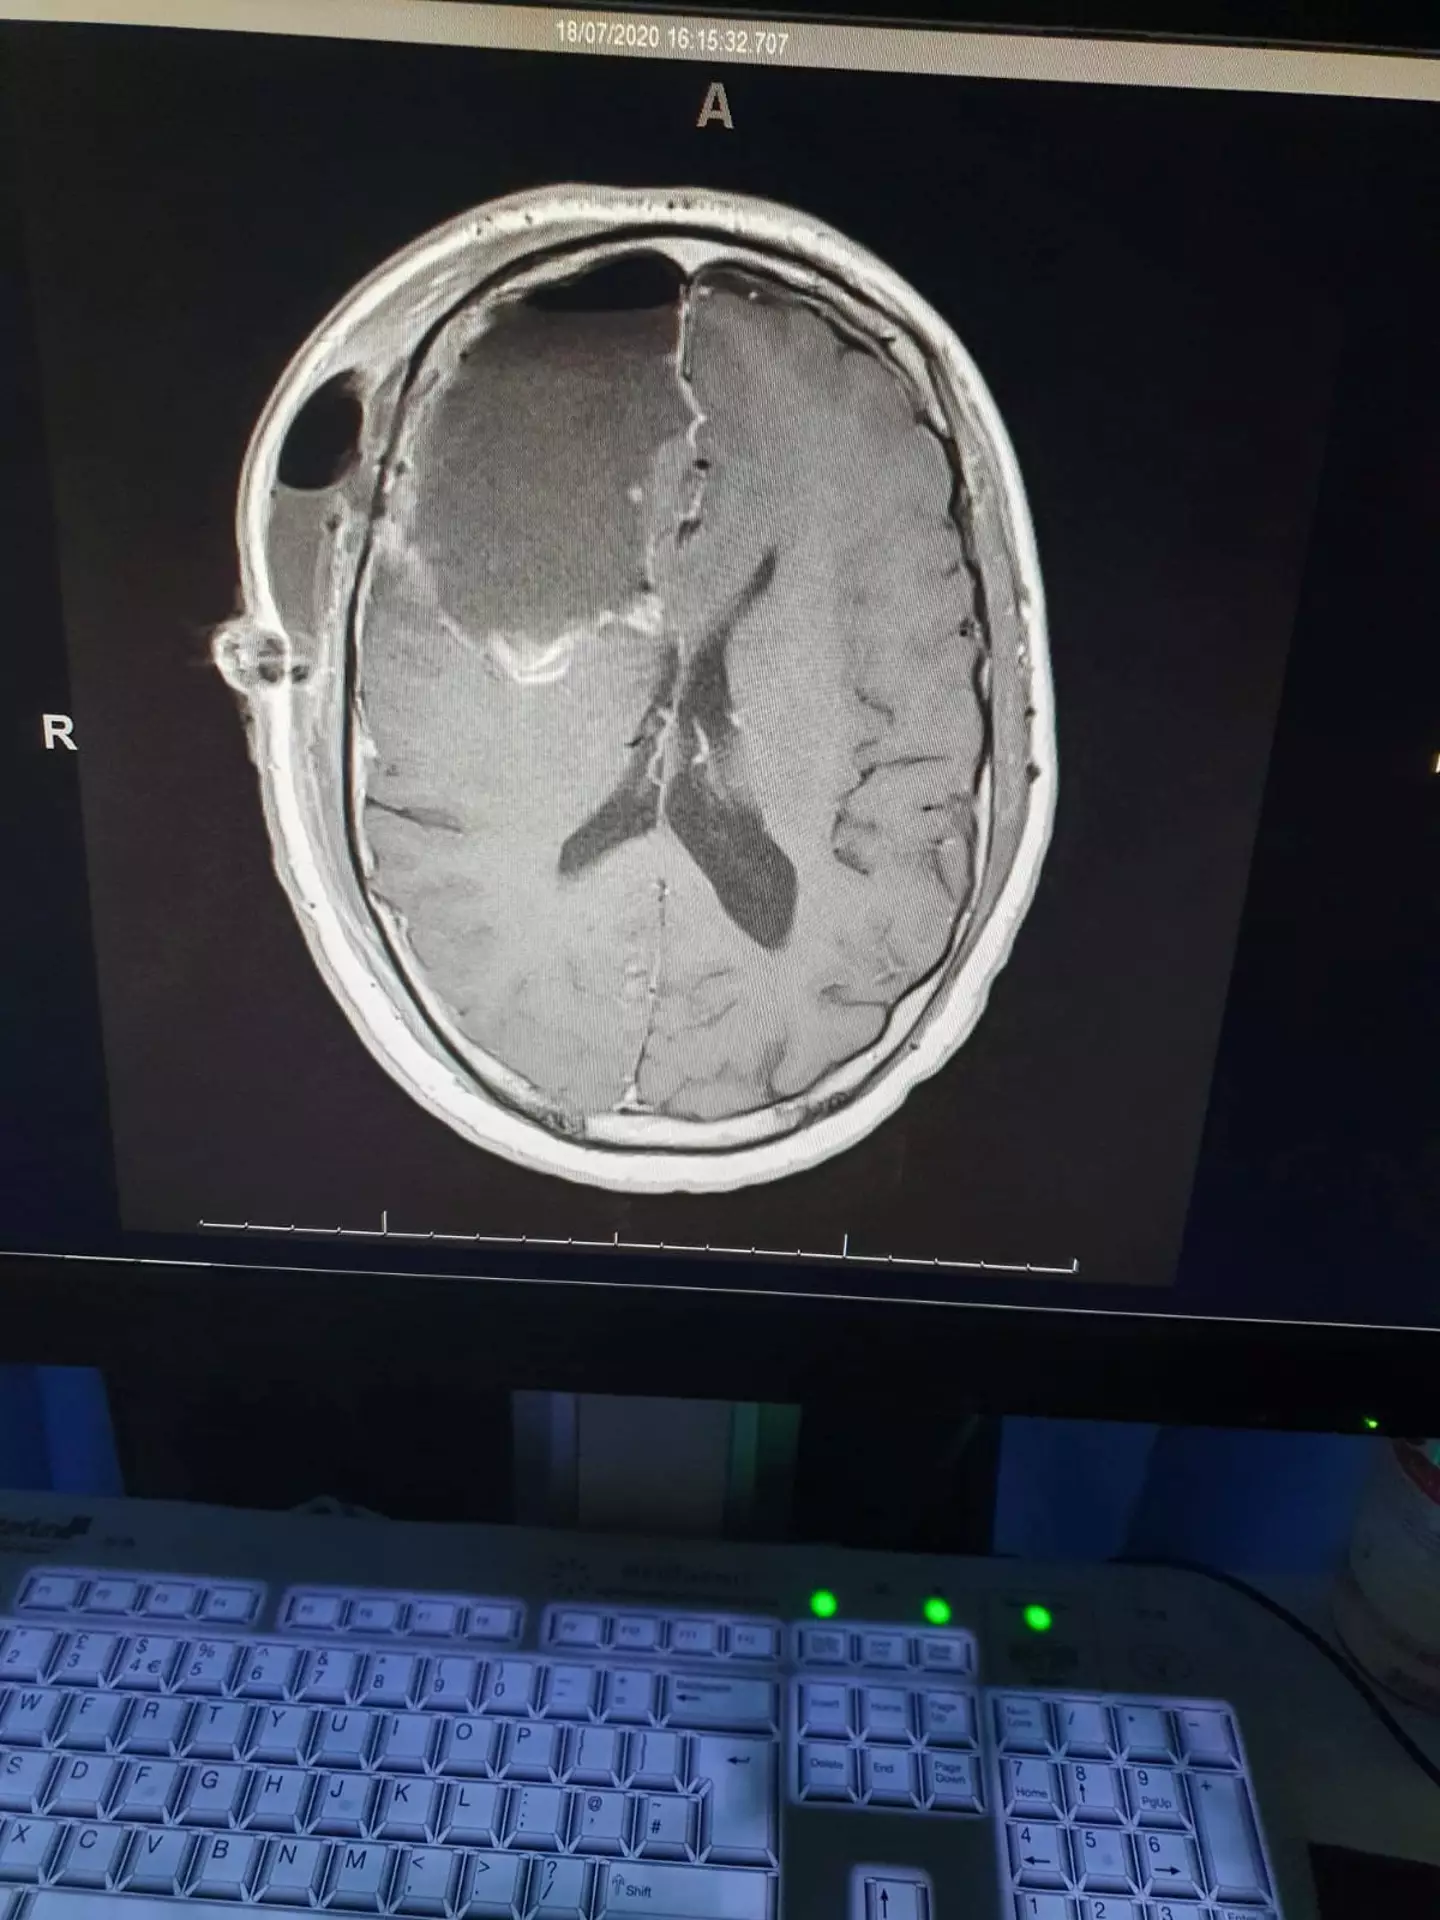

The devastating diagnosis saw Matt be referred to the Brighton Royal Hospital, where he was diagnosed with astrocytoma glioma.

"I was told it was on the left and right side of my brain and that it would become aggressive," he said.

Thankfully, the tumour was operable and in July 2020, Matt underwent a partial craniotomy, which involved removing 70 percent of the tumour on his right side - the mass they removed was the size of a fist.